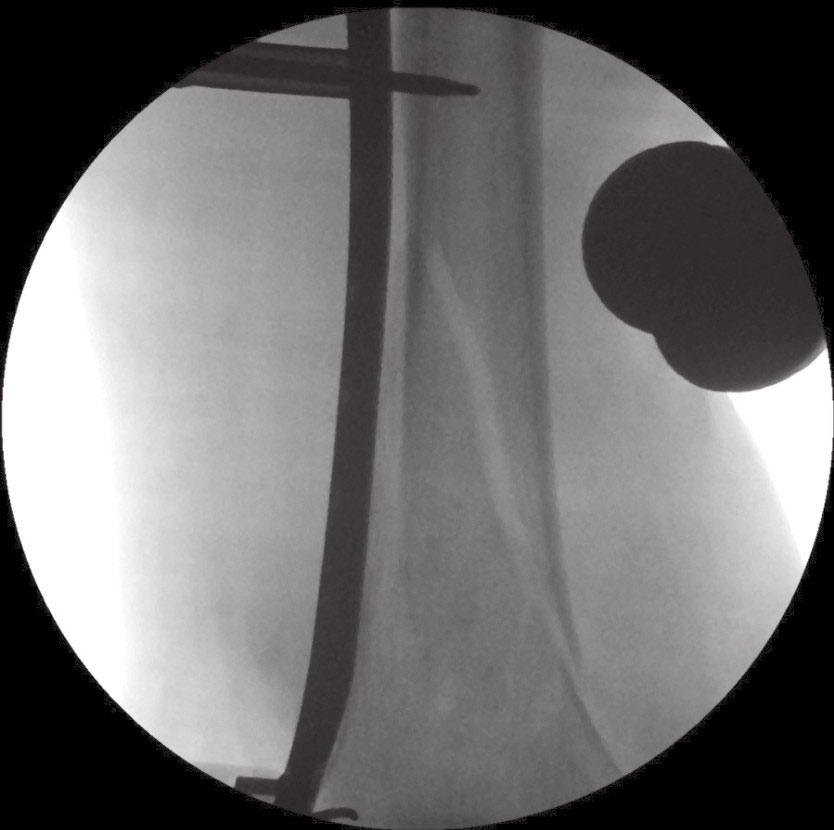

运用隧道工具或钢板在外侧肌肉下作一隧道。确定钢板长度。最佳的钢板长度应跨越骨折处并且足够长。

钢板平整放于外侧髁倾斜的平面